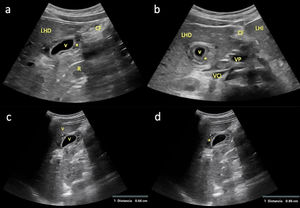

En este contexto, se presenta el caso de una adolescente de 12 años con dolor en epigastrio e hipocondrio derecho, astenia, fiebre y vómitos de 72h de evolución. La ecografía clínica mostró engrosamiento mural vesicular en «capas de cebolla» de hasta 8mm (normal <3mm), sin cálculos ni barro biliar, y sin flujo en Doppler color (fig. 1 y vídeo). Fue remitida al hospital, donde se objetivaron hipertransaminasemia, hiperbilirrubinemia y serología positiva para el VHA, diagnosticándose CAA asociada al VHA. El tratamiento conservador logró la resolución completa clínica, analítica y ecográfica (fig. 2).

a) Corte longitudinal paramedial del abdomen a nivel de hipocondrio derecho con sonda convex (1,5-4,5MHz), en el que se objetiva una sección sagital de la vesícula biliar (VB) con pared engrosada (*), sugerente de CAA; b) Corte transversal del abdomen con la misma sonda y al mismo nivel que el anterior, en el que se visualiza una sección axial de la VB con pared igualmente engrosada (*); c y d) Cuantificación del grosor mural vesicular (*) en un corte longitudinal paramedial del abdomen a nivel de hipocondrio derecho con sonda convex, en el que se observa una sección sagital de la VB con pared engrosada: c) 6,6mm; d) 8,6mm (normal <3mm). CF: cisura falciforme; LHD: lóbulo hepático derecho; LHI: lóbulo hepático izquierdo; R: riñón derecho; VCI: vena cava inferior; VP: vena porta.